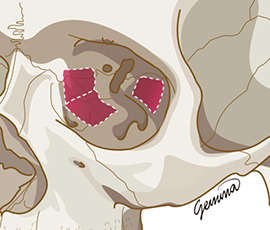

使用专用设

备进行精细截骨

(包括眼眶内壁、下壁、侧壁) -

将截骨部位

向内推移,

扩大眼眶空间 -